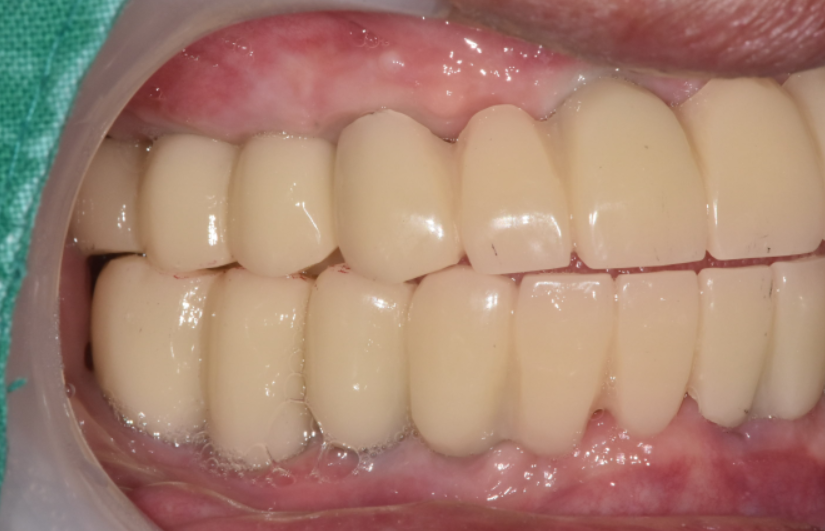

보철물을 바로 제작하기 보다

임시치아로 2주정도 사용할 수 있게 하였습니다.

이게 임시치아인데요.

나쁘지 않죠~?

이가 없다가 갑자기 들어가게 되면

턱도 놀라고

발음도 잘 안될 수 있습니다.

2주정도 임시치아를 사용해 보시면서 감도 익히시고

보철물의 모양이라던가 색깔 , 높이

환자분과 디테일한 부분들을 상의했습니다.